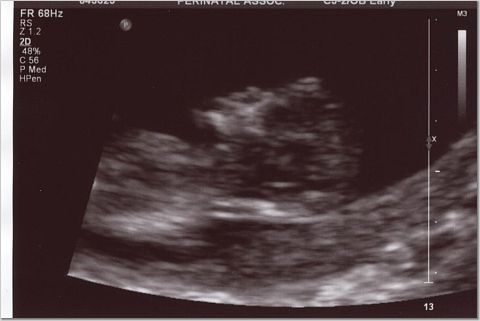

I got to watch TV with my baby as the star!!! Everything looked good and we'll have partial results on Monday. The genetic counselor really freaked us out a biut, prior to the sono. DH actually asked her to do the sono first then talk to us about what could be wrong after..he was getting really worried. But so far everything looked great, we got some pics and we scheduled our level 2 for July 12...it'll be a nice 30th b-day gift!!

Oh and the heartbeat was 178...tech told me old wives tale was higher girl..so we'll see..not buying pink yet though!! Image Attachment(s):